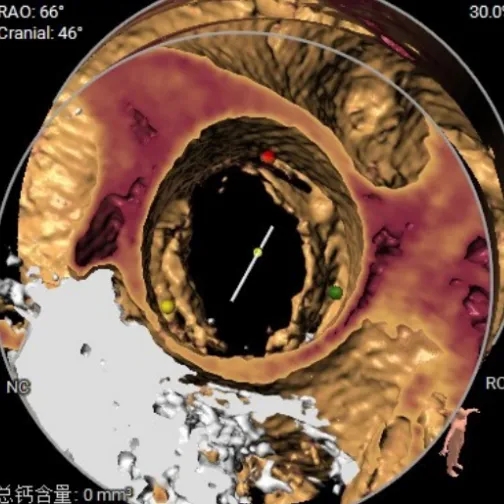

术前CT分析

患者为Type-1型二叶式主动脉瓣,无钙化

Type-1型二叶式主动脉瓣,R-L融合

瓣叶增厚,瓣上结构较大,锚定能力较低

根部结构HU850下无钙化